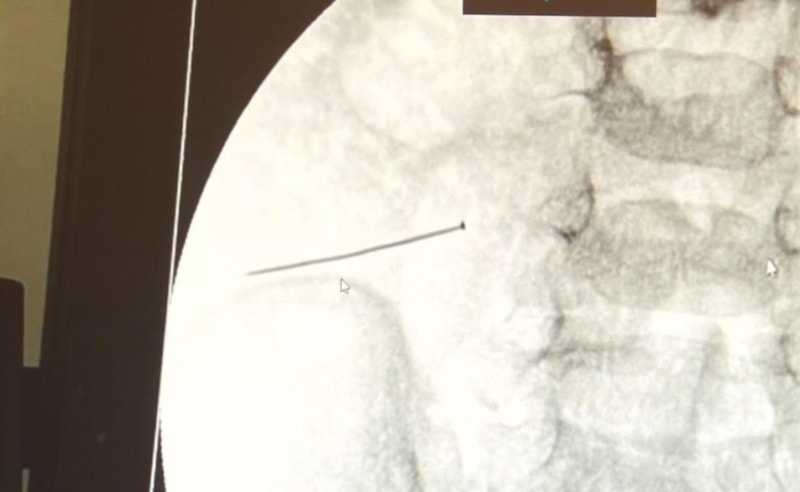

Burada yapılan tetkiklerde 2 yaşındaki çocuğun ince bağırsağında yaklaşık 3 santimlik toplu iğne olduğu ve bağırsağı deldiği belirlendi.

Görüntülemeler sonrası 30 Ekim akşamı Çocuk Cerrahisi Kliniği Eğitim ve İdari Sorumlusu Doç. Dr. Sefa Sağ ve ekibi hemen ameliyata girdi.

Başarılı operasyonla iğne olduğu noktadan alınırken aile de rahat bir nefes aldı.

Ertesi gün bağırsakta delinmeyle sonuçlanmış ve çocukta da ciddi semptomlar meydana getirmişti. Bu şekilde hasta bize başvurdu. Tetkikler sonucunda yabancı cismi tespit ettik, semptomları ve bulgularına göre de çocuğu ameliyata aldık. Yaklaşık 3 santim boyunda bir toplu iğnenin ince bağırsağı deldiğini, ince bağırsaktaki içeriğin de karın içerisine dolduğunu gördük. Ameliyatı başarılı bir şekilde tamamladık, yaklaşık 1 saat süren bir ameliyattı" dedi.

Öte yandan, yaklaşık 3 santimlik toplu iğne filme yansıyan görüntüsüyle gözler önüne serildi.